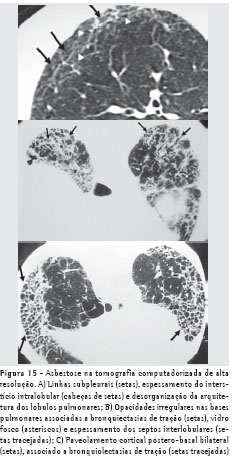

O melhor método de imagem é a TCAR. Além de aumentar a detecção das formas iniciais da doença, onde a radiografia é quase sempre normal, a TCAR permite a diferenciação da asbestose de outras alterações parenquimatosas, e redução do número de casos falso positivos e da variabilidade interobservador. Um estudo demonstrou que a TCAR revela alterações em 80% dos pacientes com radiografia normal e evidências clínicas de asbestose e em 30% daqueles sem evidências clínicas ou radiográficas. Atualmente, a maioria dos autores recomenda a TCAR em todo indivíduo com história de exposição ao asbesto e radiografia simples do tórax alterada. As principais alterações na TCAR são opacidades e linhas subpleurais, vidro fosco, espessamento dos septos interlobulares, faveolamento, distorção arquitetural e bronquiectasias de tração (Figura 15).(7)